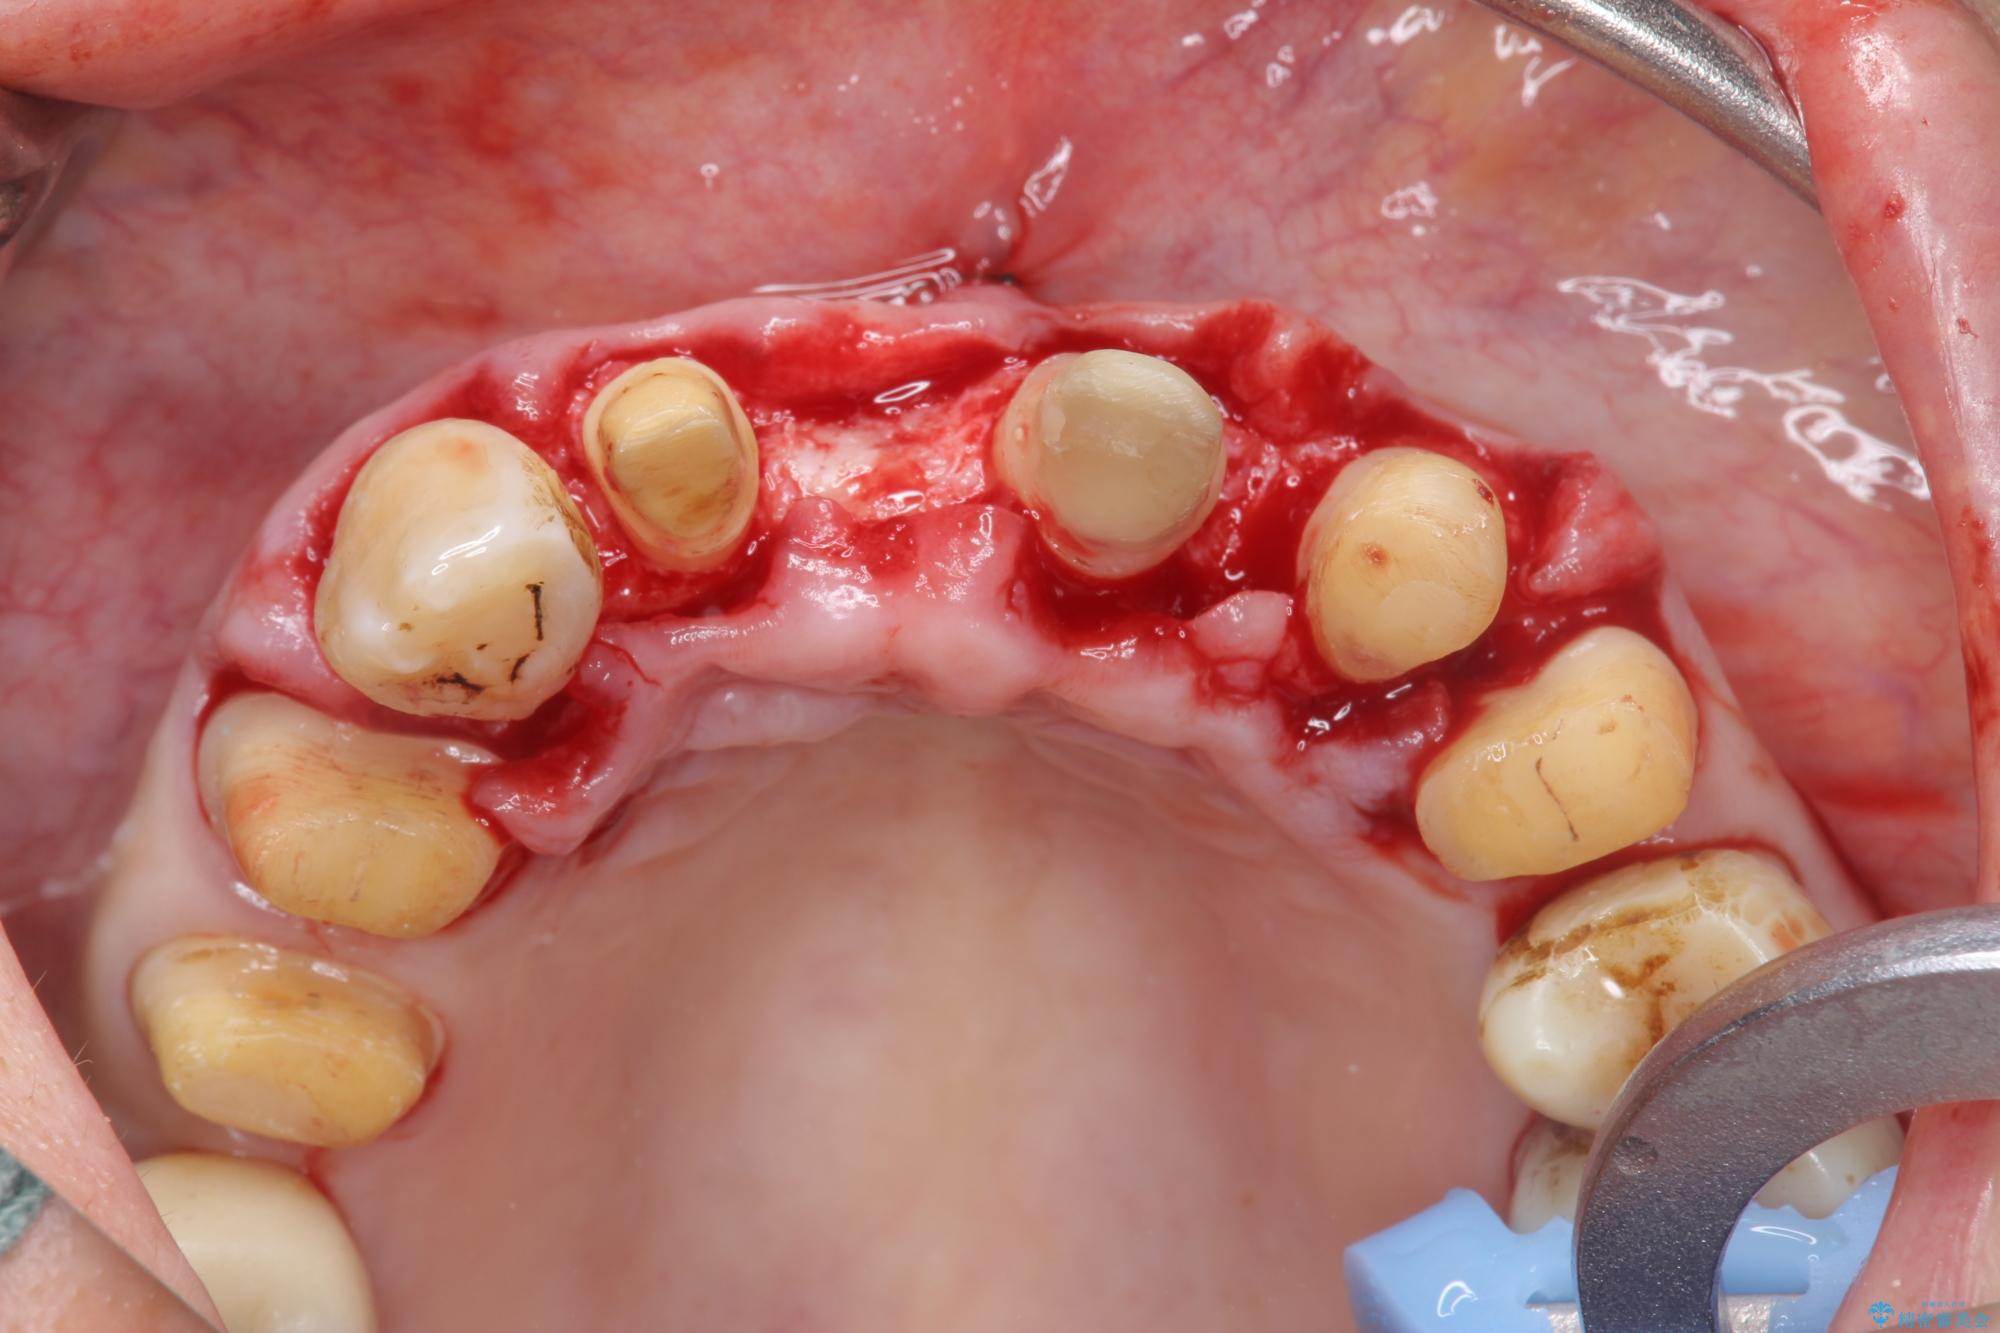

まず、保存の難しい歯を抜去したのち矯正治療を行い歯並びの改善、歯周ポケットを除去したことで安定した歯周環境、咬合関係を作り出すことができました。

治療中

歯の総合的なマネージメントを行う包括的歯科治療の実践[ 歯周病・矯正・セラミック補綴 ] 治療中画像 歯の総合的なマネージメントを行う包括的歯科治療の実践[ 歯周病・矯正・セラミック補綴 ] 治療中画像 歯の総合的なマネージメントを行う包括的歯科治療の実践[ 歯周病・矯正・セラミック補綴 ] 治療中画像 歯の総合的なマネージメントを行う包括的歯科治療の実践[ 歯周病・矯正・セラミック補綴 ] 治療中画像 歯の総合的なマネージメントを行う包括的歯科治療の実践[ 歯周病・矯正・セラミック補綴 ] 治療中画像 歯の総合的なマネージメントを行う包括的歯科治療の実践[ 歯周病・矯正・セラミック補綴 ] 治療中画像 歯の総合的なマネージメントを行う包括的歯科治療の実践[ 歯周病・矯正・セラミック補綴 ] 治療中画像 歯の総合的なマネージメントを行う包括的歯科治療の実践[ 歯周病・矯正・セラミック補綴 ] 治療中画像 歯の総合的なマネージメントを行う包括的歯科治療の実践[ 歯周病・矯正・セラミック補綴 ] 治療中画像 歯の総合的なマネージメントを行う包括的歯科治療の実践[ 歯周病・矯正・セラミック補綴 ] 治療中画像 歯の総合的なマネージメントを行う包括的歯科治療の実践[ 歯周病・矯正・セラミック補綴 ] 治療中画像